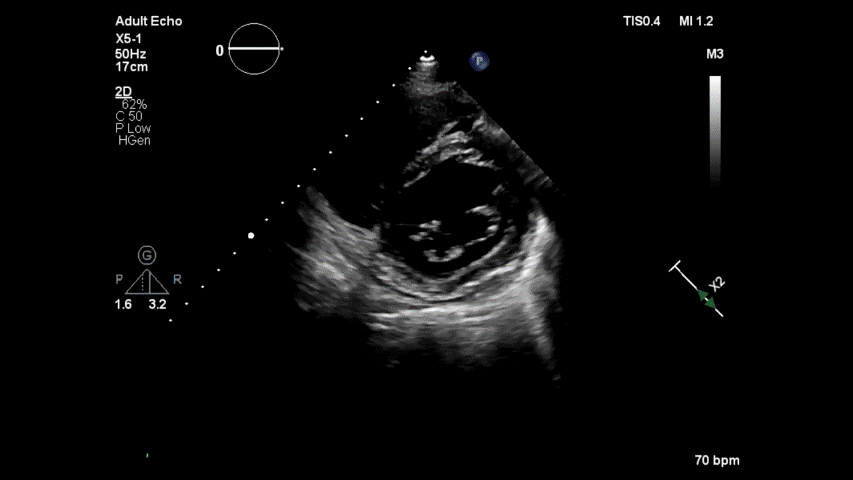

It is rare case and real tough one. A clue : concentrate inside the pericardial space. (36, year old man , asymptomatic)

Comment : Most curious , who stopped it from entering LV ?